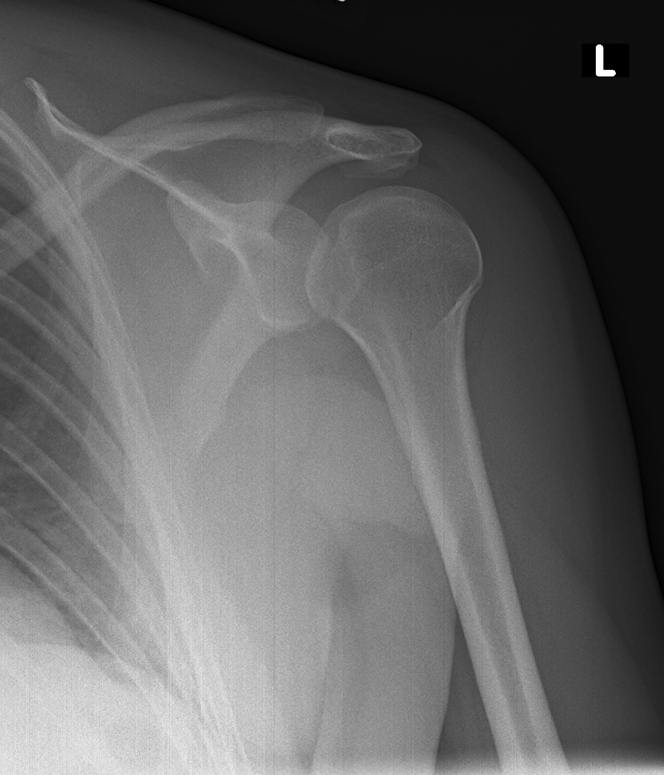

Briefly describe what is shown on the x-ray

Lightbulb Sign suggesting a posterior shoulder dislocation.

The lightbulb sign refers to the abnormal AP radiograph appearance of the humeral head in posterior shoulder dislocation.

When the humerus dislocates it also internally rotates such that the head contour projects like a lightbulb when viewed from the front.

The ‘light bulb sign’ suggests posterior dislocation, as the humerus is fixed in internal rotation.